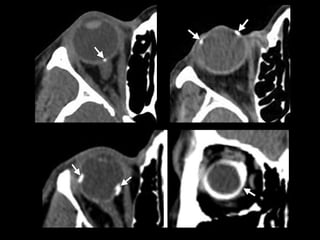

• Fx Techo orbitario

• Trapdoor

Trapdoor

Fracturas simples • FxTecho orbitario • Trapdoor